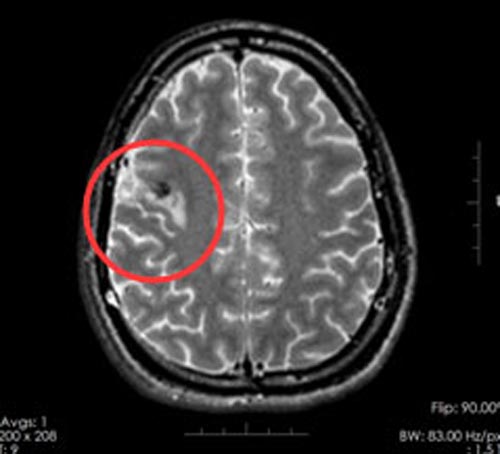

秦先生与家人来到广东三九脑科医院,一系列检查后,他被诊断为:1.右侧额叶占位,2.症状性癫痫。病灶位于脑功能区,传统的开颅手术极易造成功能区损伤,病灶切除与脑功能保护之间的权衡是一个难题。

术后,秦先生恢复很好,影像检查证实肿瘤得以全部切除,不仅抽搐症状完全消失,而且没有出现失语、偏瘫等后遗症。